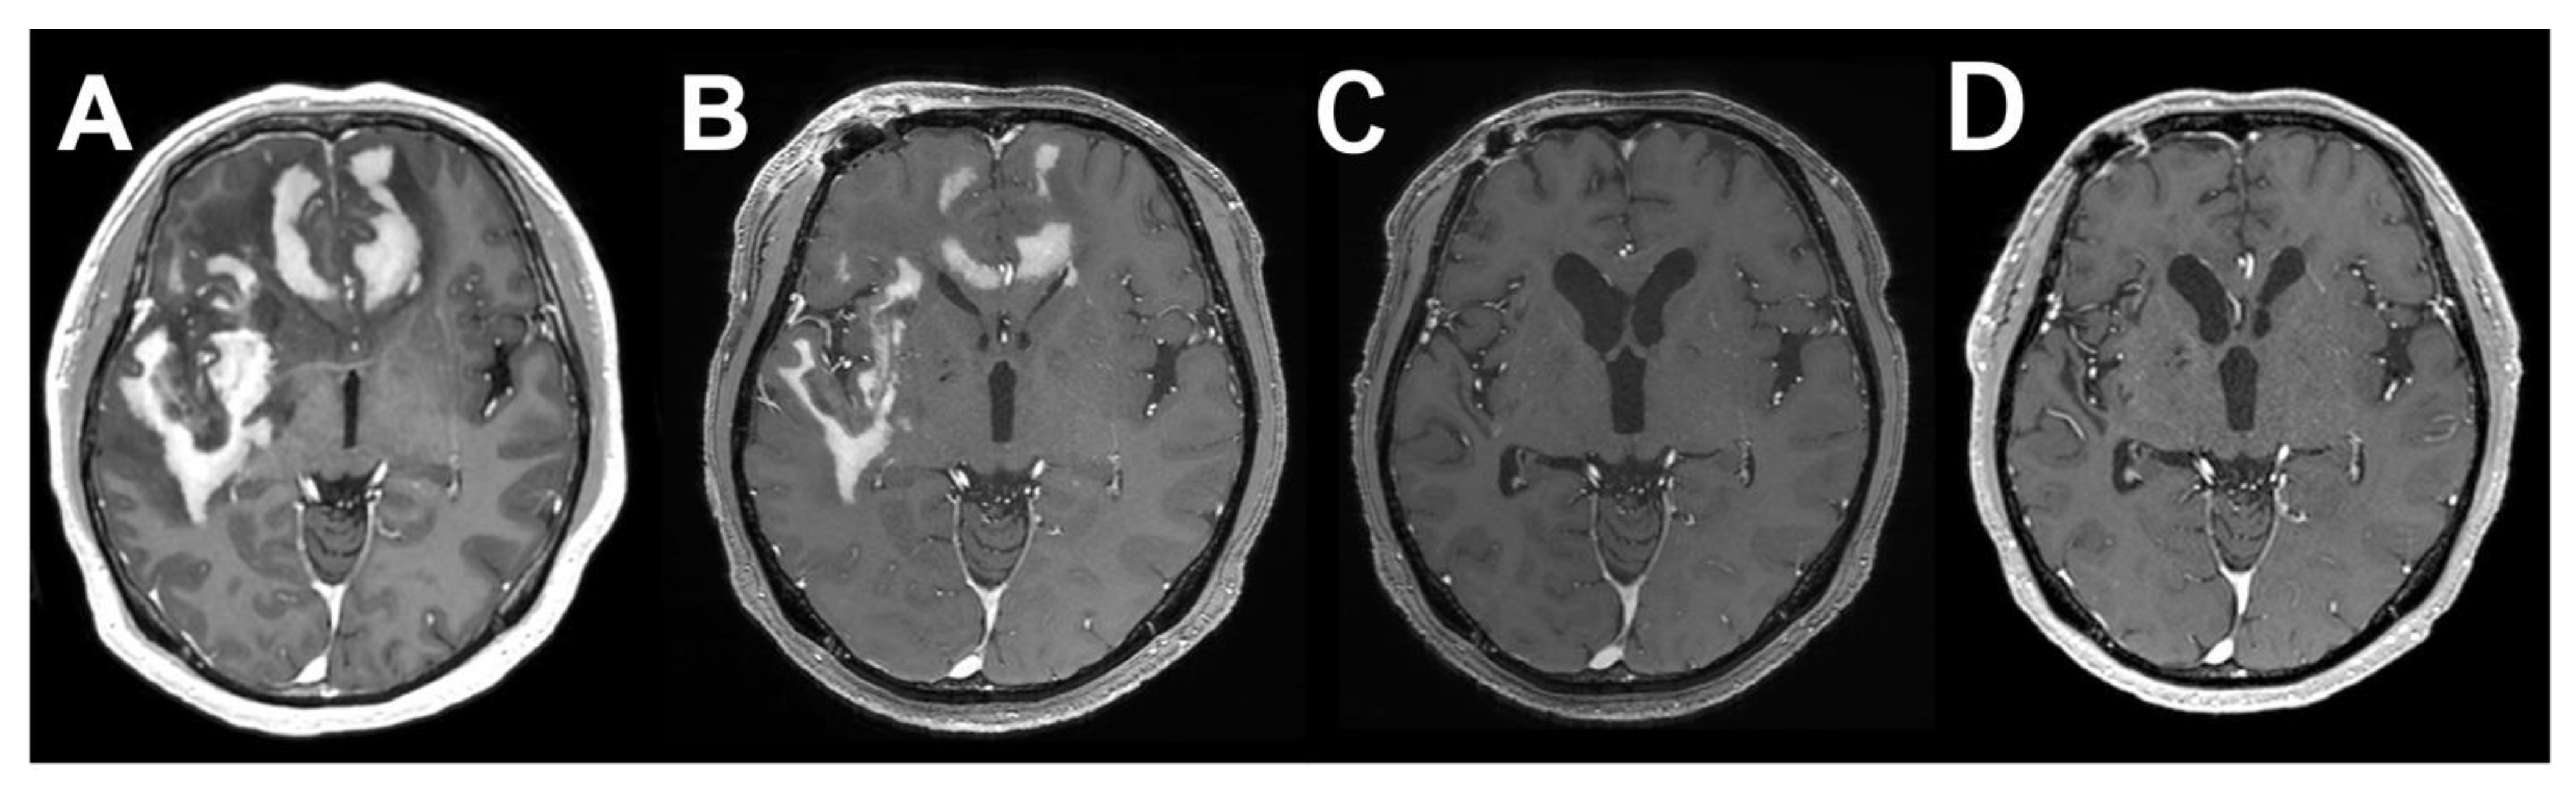

2. Case Presentation